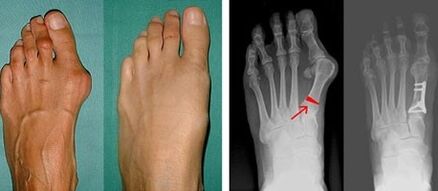

First toe valgus deformity most commonly affects women of mature age but can also affect men.A deformed thumb base is unsightly.In this condition, the person feels physically unwell and, in the advanced stages, suffers from pain.Deviation of the big toe is the result of uneven body loading on the foot.This change can adversely affect the feet and other fingers.

In the first stage of identifying big toe and little toe valgus, your doctor will perform a visual inspection.This determines the stage of development of the pathology.To determine detailed changes in the joints, X-rays and plantars are performed.

If visual examination and x-rays do not give any results, refer the patient to plantar photography to identify possible flat feet.The method involves taking fingerprints of the feet and, on this basis, making shoes or insoles with orthopedic properties for the patient.Then give the patient a pedometer.The method uses computer analysis to determine the pressure a person's weight puts on the feet.Advanced diagnostic results are the basis for choosing a treatment for first and second toe curvature.